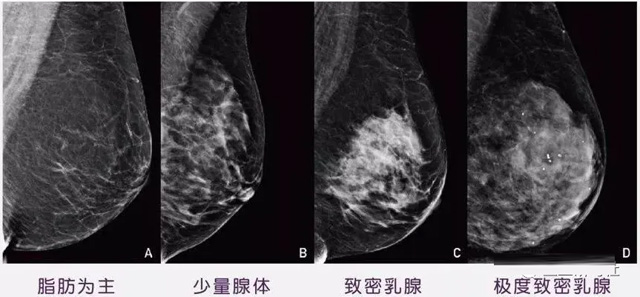

女性乳腺的自我检查,特别是注意有小结节,肿块,乳头有液体渗出情况,需要通过乳腺DR,X光线,磁共振等影像技术检查。胸的大小跟乳腺癌没多大关系,乳腺的密度大发病率高一些,胸小脂肪少致密性大。更容易乳腺癌。这个还不能通过自我检查来确认。致密乳腺组织看上去是白色或浅灰色需要通过乳腺X射线检查。

乳腺X射线有辐射,40岁以下的女性没有高危因素跟临床特征,医生都是不建议使用钼靶检查。乳腺超声无创无辐射,对乳腺组织分辨率高??梢越橄僦卓榇又旅苄腿橄僮橹星崴刹槌隼矗嗥绽漳J郊觳槿橄偌安”?,超声小于1厘米的病灶非肿块性乳腺癌检出率低。超声检查结果依赖医生水平和经验,乳腺DR超声推动乳腺超声图像的标准化,提高检查的准确率。对乳腺组织内的细小钙化灶, 从范围、乳腺X射线形态以及分布特点上进行定性诊断。造影剂增强型乳腺X线摄影静脉注射碘化造影剂结合乳房X线摄影。磁共振MRI对乳腺癌研究的深入对软组织具有较高的分辨率等特点,在临床上被广泛认可。乳腺CT的探测器围绕着乳房成像,无痛无挤压,3D乳房图像乳腺病灶的大小、数量、形状、位置以及血管分布。一次扫描可创建多达两千张投影图像 。乳腺PET,适合普通人群和乳腺癌高危人群早期检测,发现极早期微小病灶并明确定性。